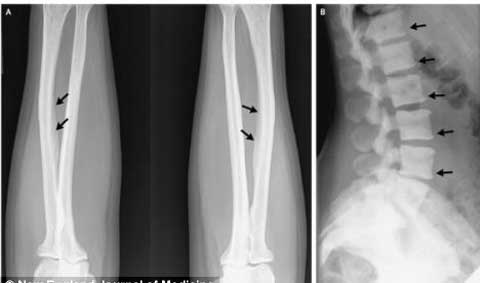

Kết quả x-quang cho thấy chất flour đã tạo nên những mảng khoáng bám trên xương của bệnh nhân khi cô uống quá nhiều trà

Kết quả X-Quang cho thấy xuất hiện những vùng dày đặc bất thường trên xương sống và sự vôi hóa các dây chằng ở cánh tay cô.

Lượng flour trong cơ thể cô cao gấp 4 lần tỷ lệ thông thường. Các bác sĩ điều trị cho người phụ nữ này cho biết chứng bệnh xương nhiễm độc flour là vô cùng hiếm gặp ở các nước Châu Âu.

Các bác sĩ này cũng nói thêm rằng, mặc dù flour là chất giúp giúp răng khỏe hơn và ngăn ngừa sâu răng, nhưng với sử dụng với hàm lượng quá lớn tới hơn 20mg một ngày như bệnh nhân này thì thận không thể xử lý được hết vì vậy chúng tạo thành mảng dạng khoáng bám lên xương khiến cô bị đau nhức và tê cứng các xương.